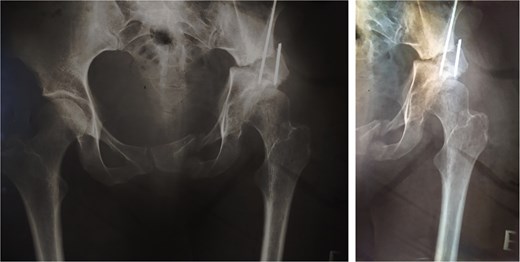

At 20-year follow-up, she presented with symptomatic hip pain. Pelvic radiographs (Fig. 2) showed signs of moderate osteoarthritis in the left hip (Tönnis Grade III). Radiographs showed signs of acetabular retroversion (ischial spine sign and posterior wall sign).

Postoperative radiographs of the pelvis 20 years after pelvic osteotomy, showing signs of moderate osteoarthritis in the left hip (Tönnis Grade III), and radiographic evidence of acetabular retroversion (ischial spine sign and posterior wall sign).